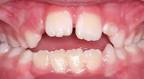

Kinywa cha mtoto hukua umri ukiwa unaongezeka na meno ya utu uzima yanapokua yanaanza kujitokeza kinywani. Unyonyaji wa vidole gumba huathiri  vitu vifutavyo;

• ukuaji wa kinywa

• mpangilio wa meno

• ina uwezo wa kubadilisha muundo wa taya ya juu.

Ukubwa wa matatizo haya hutegemea na nguvu inayotumika kunyonya vidole. Kuna watoto ambao huegesha tu kidole kwenye midomo(lips) bila kukinyonya hawa athari zao huwa ndogo sana ukilinganisha na wale ambao hunyonya vidole vyao kwa nguvu na hua athari zake zinaweza kuonekena mapema zaidi hata wakati meno ya utu uzima hayajaanza kujitokeza.